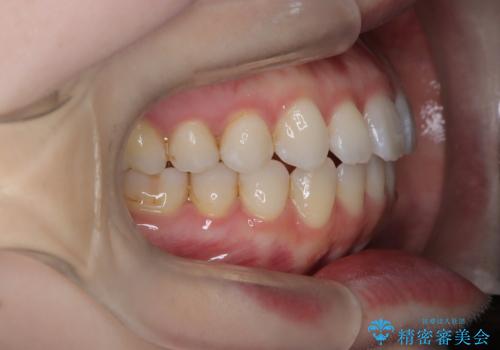

【インビザライン】がたつきをなおしたい

- 上下の前歯の凸凹が気になり、来院されました。

インビザラインで綺麗に仕上がり、満足していただきました。